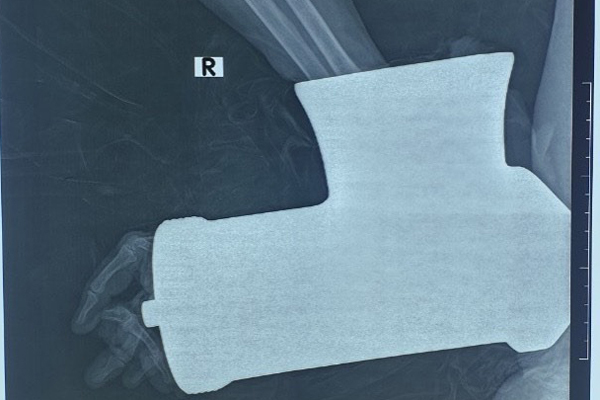

Bệnh nhân đến viện với chiếc máy xay thịt nuốt trọn bàn tay phải

Hình ảnh cánh tay cùng chiếc máy xay thịt trên phim chụp X-quang

BS Nguyễn Bá Minh, Khoa Chấn thương Chi trên và Vi phẫu thuật cho biết, bệnh nhân nhập viện trong tình trạng tỉnh, không sốt. Bàn tay phải kẹt trong máy xay thịt, dập nát phức tạp, khả năng đứt lìa bàn tay phải. Các ngón tay ở bàn tay phải mất vận động, mất cảm giác, lạnh.